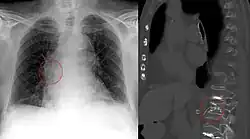

- Lungenembolie (= venöse Embolie): Der Embolus stammt aus Körpervenen und verstopft nach Passage der rechten Herzhälfte Lungenarterien.